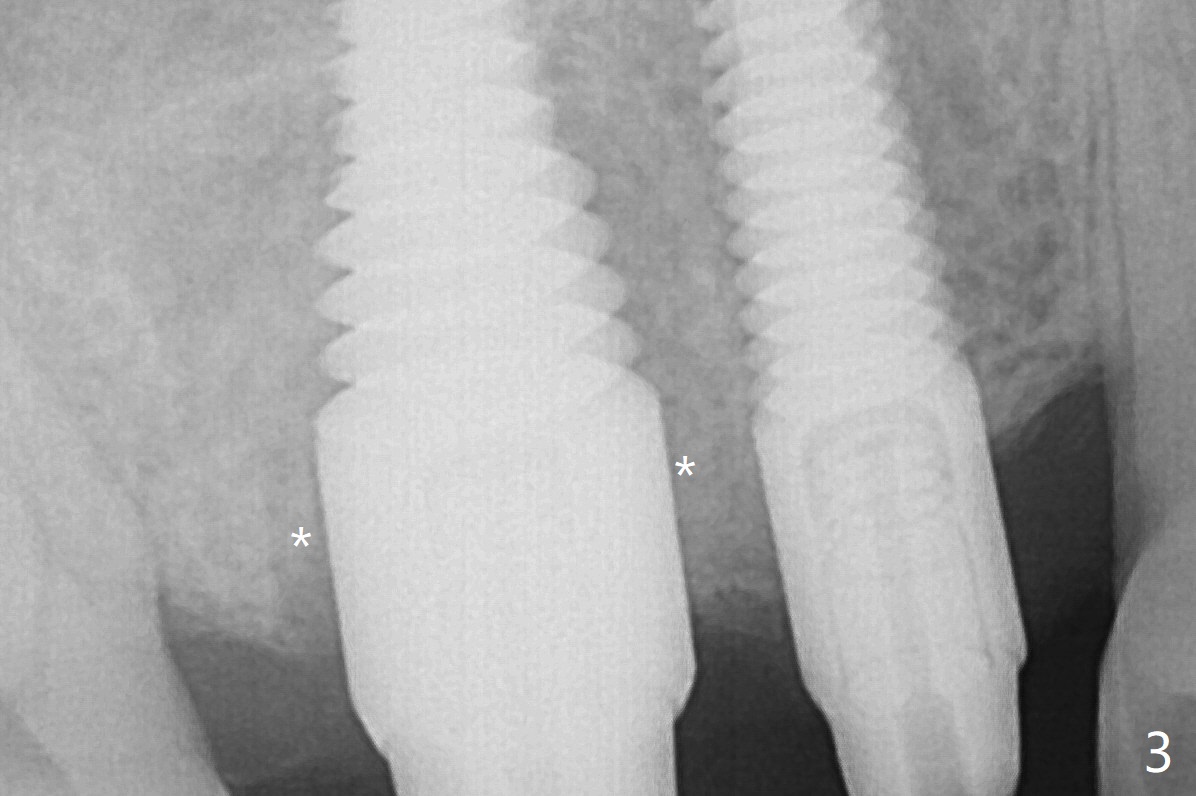

In fact the bone density at the edentulous area (#4) is high. Drills are used to finish placing a 4x17 mm tissue-level implant (Fig.3). No allograft is used for sinus lift at this site.

With proper manipulation, a 6x14 mm implant is placed at #3 with primary stability (Fig.3). The sinus membrane is perforated at #3, which is repaired with Osteogen plug without bone graft prior to implantation. Vera Graft (*) is used for closure of the socket spaces. No gap exists 7 months postop (Fig.6). The implants are placed close to each other, vulnerable to periimplantitis if oral hygiene is not maintained.